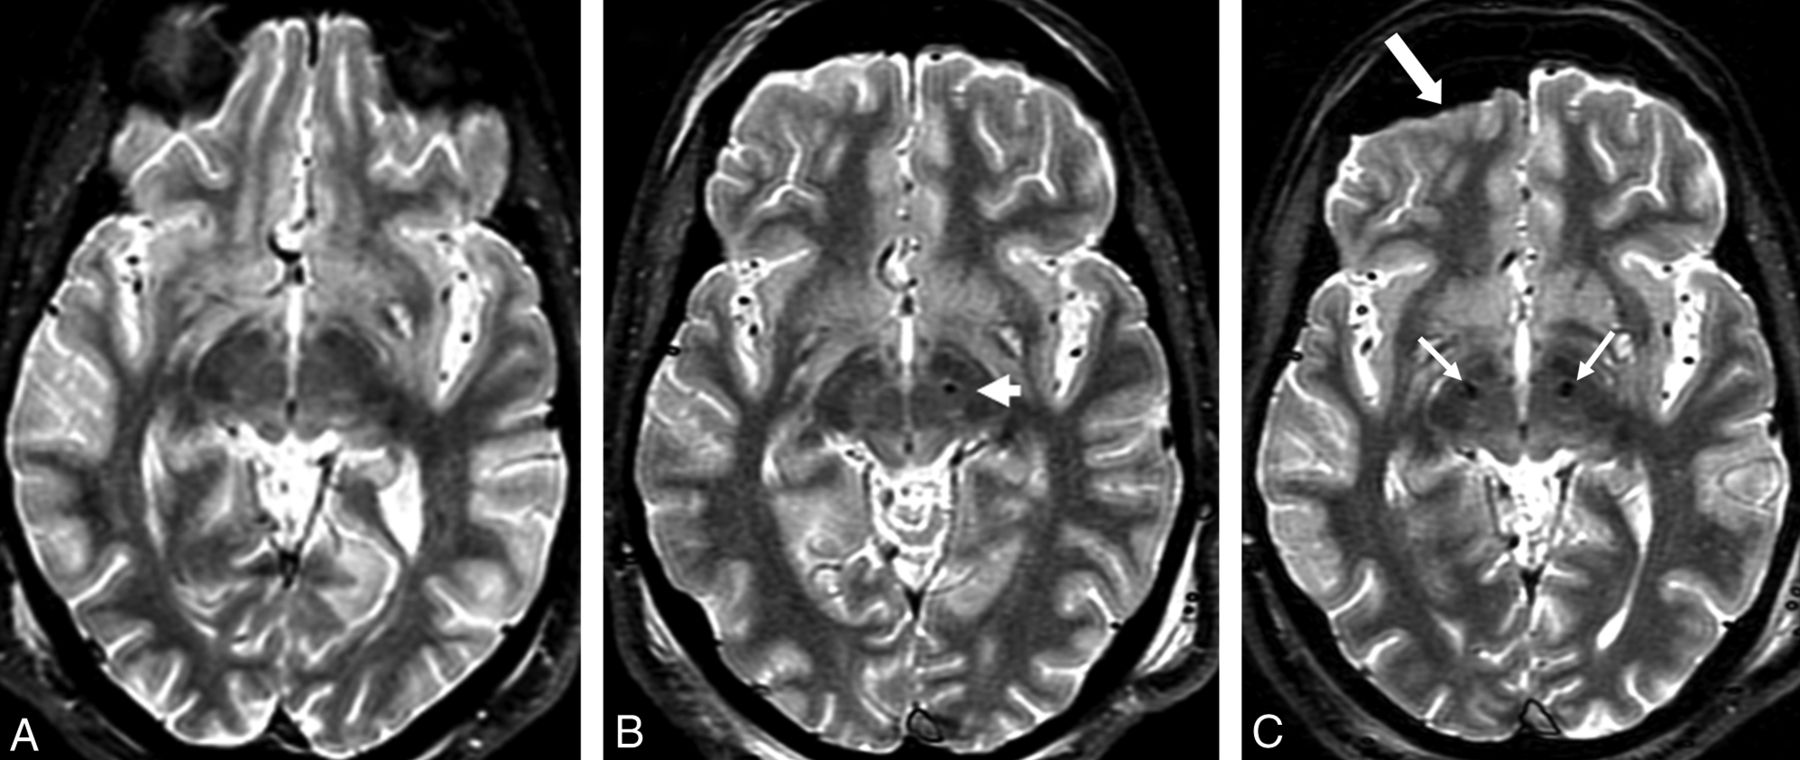

FSTIR 2D image sections for a typical patient scanned in 3 sessions. A, Presurgical high-SAR FSTIR image (1.5 W/kg) with interleaved 3-mm sections to plan for the first DBS implantation. B, Subsequent presurgical low-SAR FSTIR image (0.1 W/kg) to plan for the second DBS implantation. The arrow shows the first DBS tip at the desired location of the left STN. C, Low-SAR (0.1 W/kg) FSTIR image from the third session after a second lead implantation, to localize bilateral electrodes (arrows), visualize subcortical structures, and assess potential complications. Note the pneumocephalus (thick arrow), not uncommon during DBS implantation.